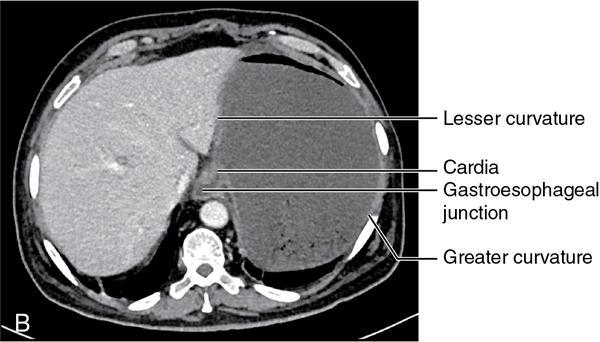

CROSS SECTIONAL ANATOMY OF ABDOMEN Satya Jha NORMAL ANATOMY OF ABDOMEN AND PELVIS Amandeep Singh The two major surfaces: The anterior and posterior layers of the coronary ligament converge on bare area (not covered by peritoneum). Its right and left margins form the right and left triangular ligaments. The right triangular ligament extends toward the diaphragm and separates right subphrenic space from right subhepatic space. The left triangular ligament gives tracts extending to the diaphragm and falciform ligament and does not compartmentalize the left subphrenic space. Ligamentum teres or the obliterated umblical vein is contained in falciform ligament which attaches the liver to anterior abdominal wall. The main portal vein, the proper hepatic artery and the common bile duct are contained within investing peritoneal folds of hepatoduodenal ligament at the porta hepatis (Fig. 7.2.2.1). Liver is divided into eight segments which are functionally independent and have their own vascular supply and biliary drainage. Arterial circulation: The branches of the hepatic artery accompanying the portal veins. Hepatic venous system: The right, middle, and left hepatic veins draining into IVC (Figs. 7.2.2.2 and 7.2.2.3). The gallbladder is a blind pear-shaped muscular membranous sac which is an embryologic derivative of the foregut, is a pouch lying along the undersurface of the liver. The gallbladder fossa is located in the plane of the interlobar fissure, which lies between the right and left hepatic lobes. Its major function is to store and concentrate bile which is produced by the liver. It measures approximately 4 cm in diameter when it is normally distended. Gallbladder is a smaller tubular structure in contracted state. The normal gallbladder wall thickness ranges from 1 to 3 mm. The gallbladder is divided into the fundus, body and neck. Infundibulum is present in the region of neck of the gallbladder, which is called the Hartmann pouch, where gallstones are usually impacted. Intrahepatic biliary radicles (IHBRs) scattered throughout the liver get confluent towards the hilum. They unite to form the right and left main hepatic ducts which further unite to form common hepatic duct (CHD) at the hilum. Common bile duct is formed by the union of cystic duct with common hepatic duct. The main pancreatic duct is joined with the common bile duct to form the ampulla of Vater at the major duodenal papilla (Figs. 7.2.2.4 and 7.2.2.5). Pancreas is located in anterior pararenal space of retroperitoneum anterior to perirenal (Gerota’s) fascia and posterior to parietal peritoneum. It is divided into head, uncinate process, neck, body and tail from right to left. Pancreas lies anterior to portal vein, which marks the point of transition between the body and neck. The region between head of pancreas and second and third parts of duodenum is known as the pancreatic groove. In postnephrectomy cases or with agenesis of kidney or ectopic kidney, pancreas moves posteriorly to partially fill in the empty renal fossa; its soft tissue density should not be mistaken for recurrent tumour. It is located in the pancreatic groove and is bounded superiorly by the duodenal bulb, laterally by second portion of duodenum, inferiorly by third portion of duodenum, medially by superior mesenteric vein and anterior to inferior vena cava. It is a wedge or wedge shaped lying posterior to superior mesenteric artery and vein. It is an imaginary junction between the head and body and lies directly over the junction of the splenic vein and superior mesenteric vein. It is located posterior to the lesser sac and anterior to the aorta, left adrenal gland, left kidney, and renal vessels and runs obliquely upward to the left of the superior mesenteric vessels. It is situated median to the colonic flexure and anterior to the left kidney. It is located in close proximity to the splenic hilum without a notable relation with the body of pancreas. It is seen anterior to the left kidney and median to the colonic flexure. The distal part of the tail passes between the peritoneal layers of the splenorenal ligament (Fig. 7.2.2.6 and 7.2.2.7).